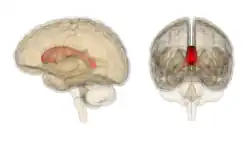

Sagittal section of a brain, front part to the left. The corpus callosum can be seen in the center, in light gray

The corpus callosum forms the floor of the longitudinal fissure that separates the two cerebral hemispheres. Part of the corpus callosum forms the roof of the lateral ventricles.[5]

The corpus callosum has four main parts – individual nerve tracts that connect different parts of the hemispheres. These are the rostrum, the genu, the trunk or body, and the splenium.[4] Fibres from the trunk and the splenium, known together as the tapetum ("carpet"), form the roof of each lateral ventricle.[6]